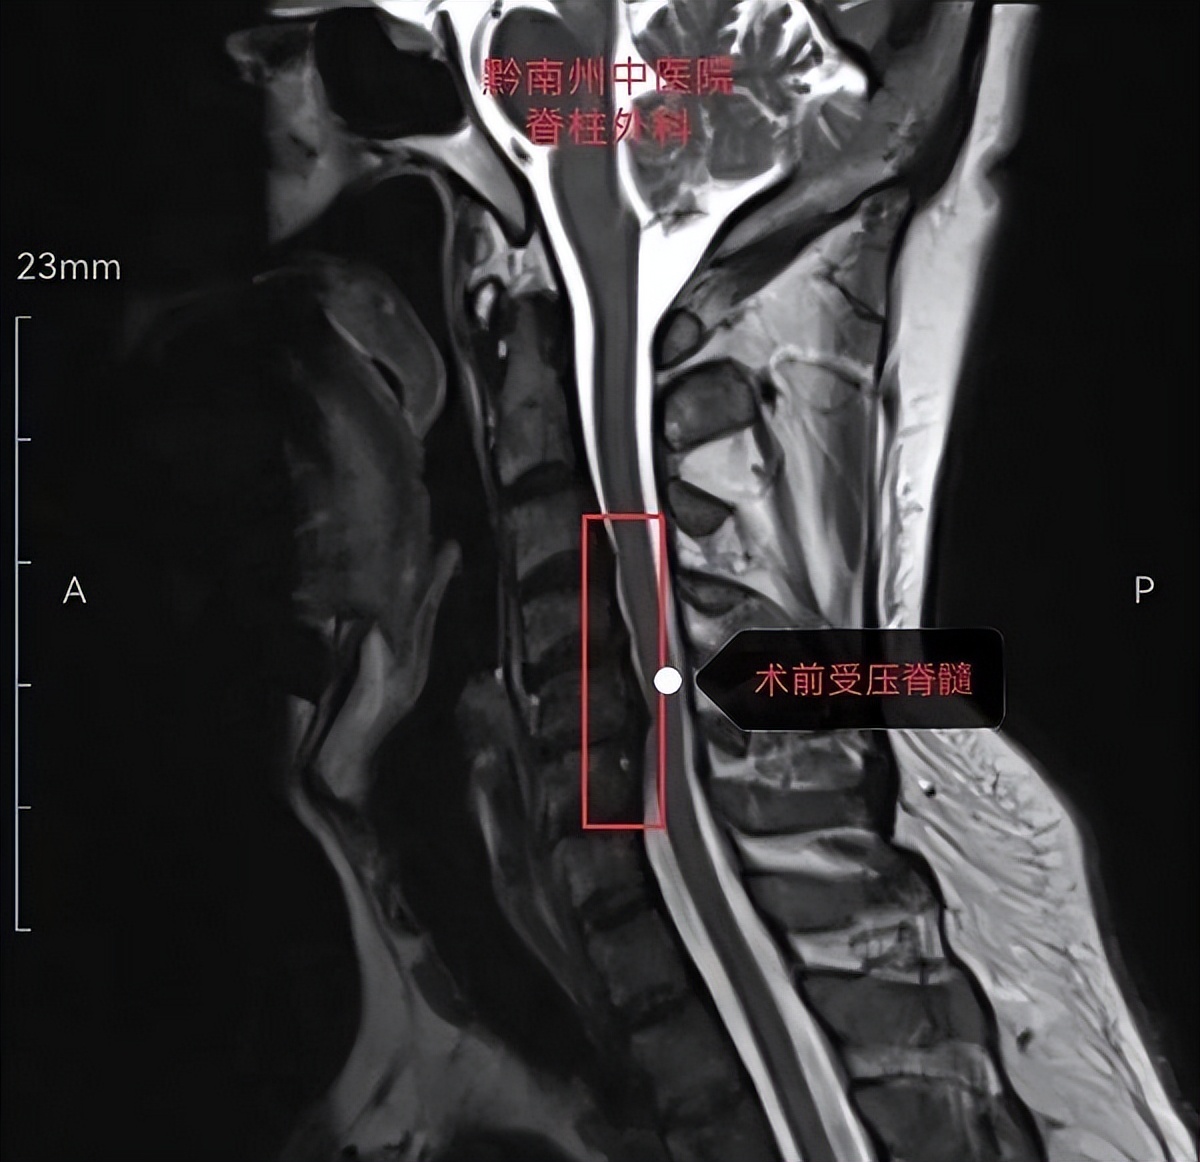

患者男性,49岁,因颈肩部及右上肢放射痛1+月入院。入院后对患者进行了详细的病情问诊、细致的体格检查以及整合患者所有影像学检查,诊断为神经根型颈椎病。同时患者还因为存在颈椎第5节后纵韧带骨化而导致脊髓收到了明显压迫。对患者进行系统保守治疗后,患者仍感到颈肩部及右上肢放痛没有明显缓解,因此向患者告知手术治疗方案。经过和患者及其家属详细交流病情后,患者和家属表示要求通过手术治疗,不仅缓解右肩部和右上肢的疼痛感,同时可以缓解脊髓的压迫,避免出现脊髓损伤而导致瘫痪的风险。

在患者和家属要求手术治疗后,脊柱外科病区主任程刚副主任医师立即组织全科室进行病情讨论,认为根据该病人的病情、影像学检查结果来看,符合目前为止最新改良颈椎前路手术术式之一的“颈前路椎体X型截骨融合术”,并且引导全科对手术实施过程进行了严密的设计。一切准备就绪后,对病人实施了该项手术。